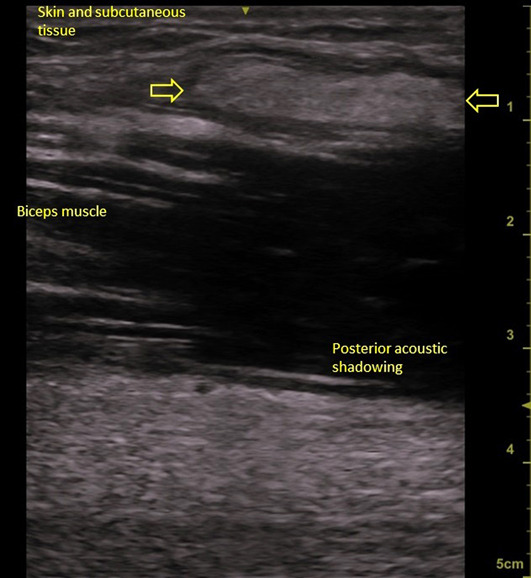

笔者同时对其进行了磁共振成像和超声检查(图2和图3),表明注射材料使二头肌浸润。手术切除受损的组织(图4)。病理检查可见异物巨细胞反应。患者返回原籍国之前未报告进一步的不良反应(图5)。

图3.使用线性探针以10 MHz的频率在长轴视图中对右前上肢同一患者的肌肉骨骼超声进行成像。黄色箭头指向受损的组织